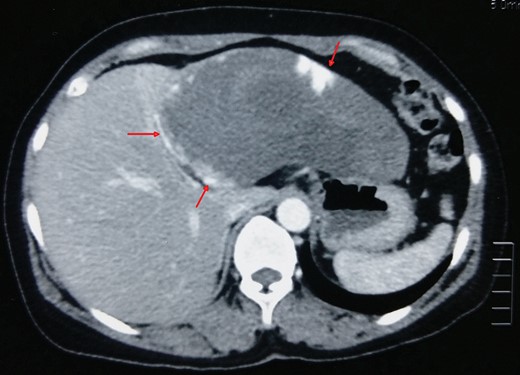

A 49-year-old female, with no co-morbid illness, presented with 3 months history of fever. The fever was intermittent, low grade (maximum temperature recorded 101 degree Fahrenheit) with an evening rise and not associated with chills and rigor. She denied any history of pain abdomen, cough, dysuria, joint pain, weight loss or loss of appetite. General physical examination including chest did not reveal any significant findings. On palpation of abdomen, there was a vague, non-tender, ill-defined lump in the epigastric region. Laboratory investigation including hemoglobin (12.6 gm/dl), total leukocytes counts (9200 cells/mm3), renal and liver function tests were within normal range. Blood cultures, sputum and urine culture were sterile. Moreover, the extensive infectious and immunological workup including tuberculosis, malaria, kala-azar and HIV were negative. Chest X-ray was also normal. The contrast enhanced computed tomography of abdomen revealed a peripheral nodular enhancing lesion measuring 15 cm × 11 cm, with central hypodense areas in left lateral segment of the liver suggesting giant hemangioma (Fig. 1). Liver hemangioma as a cause for fever of unknown origin was assumed (after excluding all other causes) and underwent laparoscopic assisted left lateral segmentectomy (Fig. 2). Histopathological report confirmed cavernous hemangioma of liver (Fig. 3). Patient did well and was discharged on postoperative Day 5. At 3 months of follow-up, patient was afebrile.

A giant hemangioma (15 × 11 cm) with central hypodense areas in left lateral segment of liver (arrow).